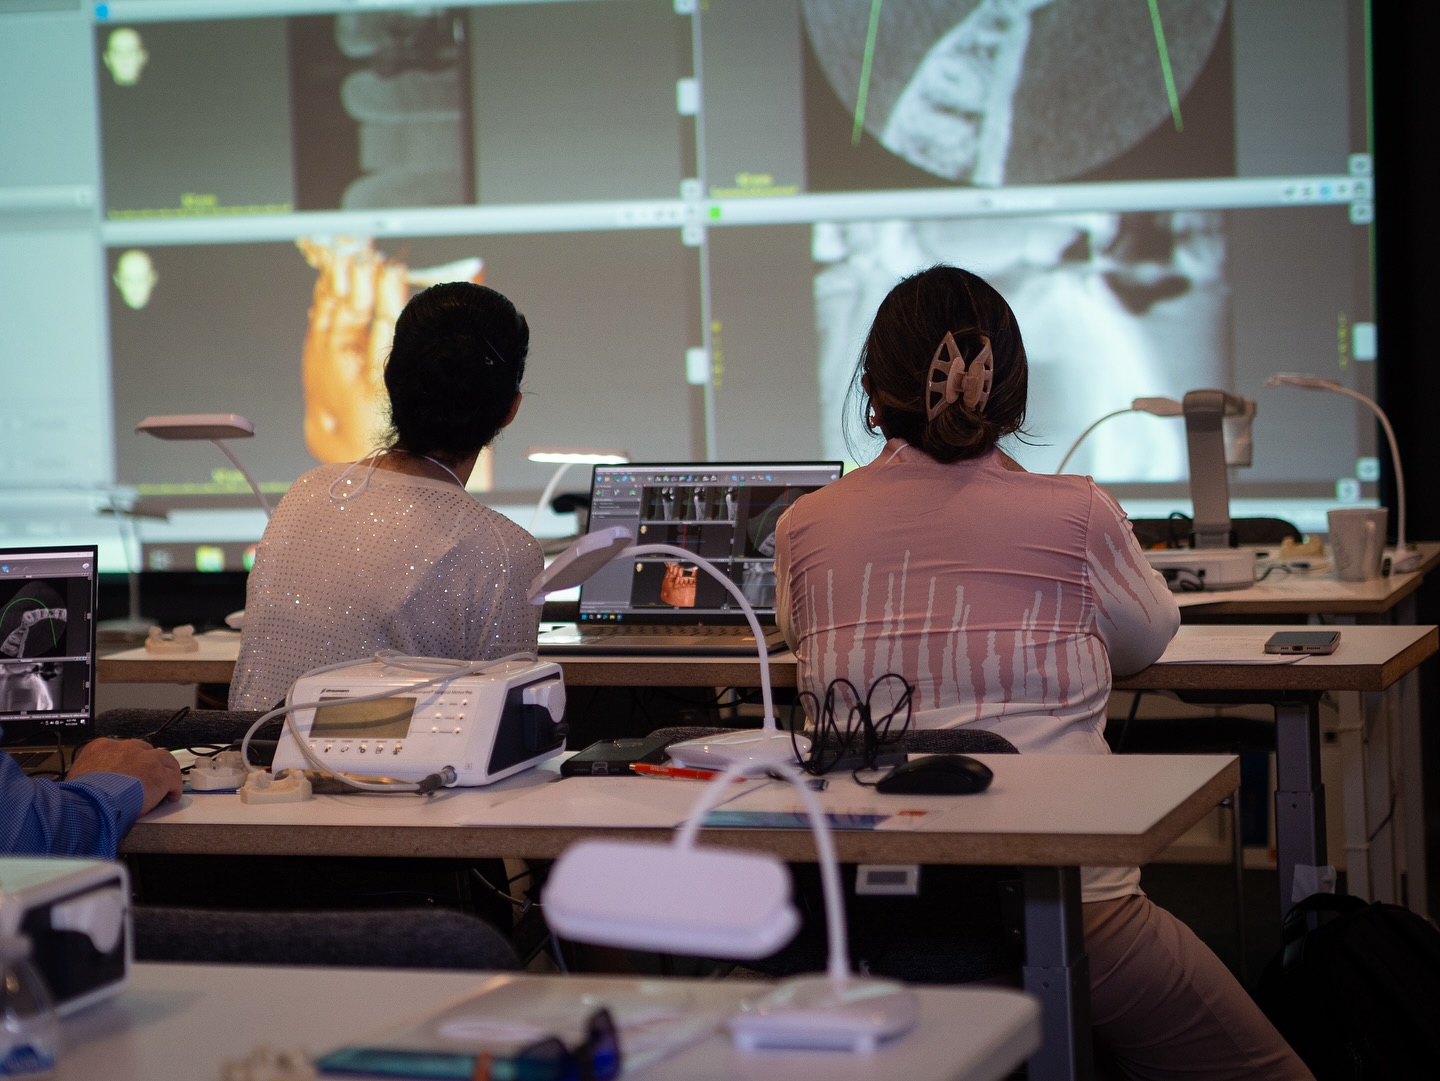

The gIDE GBR-GTR course offered excellent hands-on training, modern multimedia teaching, and live surgery demonstrations. It proved gIDE’s leadership in global dental education.

1/2 Day Interactive Lecture and 1/2 Day Hands-On workshop on fresh upper porcine models.

1/2 Day Interactive Lecture and 1/2 Day Hands-On Workshop on goat maxilla models